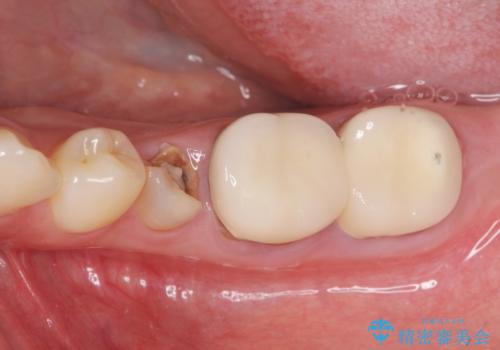

深い虫歯 歯周外科を併用した精度の高い補綴治療

- 治療途中で放置してしまった歯の治療の再開を希望され来院されました。

虫歯を除去すると、歯ぐきよりも深い虫歯であることが判明したため歯周外科を行い問題を解決していきます。